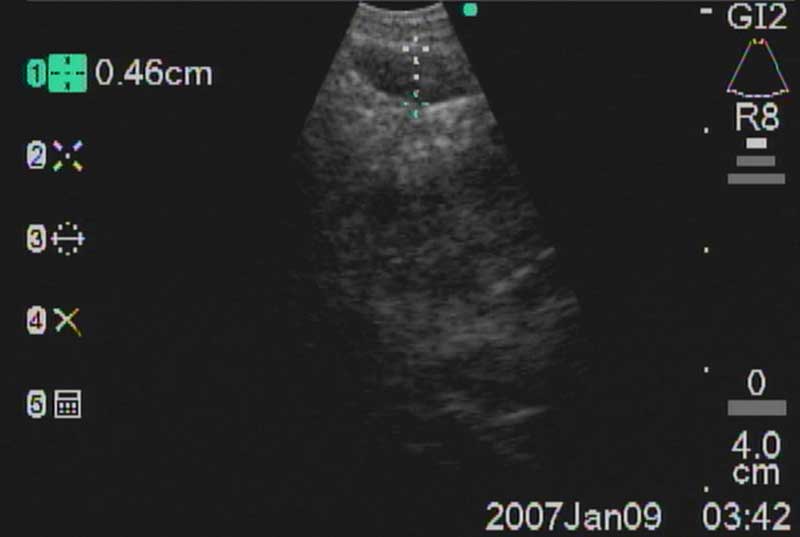

The easiest place to start ultrasound imaging is generally the right main bronchus and subcarinal areas. Pass the scope to the right side of the carina with the probe facing anteriorly and apply to the anterior wall of the RMB. This will bring into view the right main pulmonary artery. Vascular structures appear hypoechoic and pulsatile, and are usually readily discernable without using the color Doppler. If doubt persists flow within can be confirmed by switching to the Doppler overlay (B/CPD; Figures 5 and 6). Turn the scope 90 degrees counter-clockwise. This allows visualization of the subcarinal area from the right side. By moving the scope in and out the level 7 subcarinal node can usually be identified. If not, repeat this procedure in the LMB turning the scope 90 degrees clockwise instead. Once the subcarinal nodes are visualized it is relatively easy to identify other landmarks, by correlating anatomical location with the ultrasound image. It is useful to attempt to map out all nodes that you wish to biopsy first, before needle tract bleeding confounds the fiber optic image. The size of the node can be measured by freezing the US image [Freeze] and using the [Measure/Select] button and cursor scroll ball (Figures 5 and 7).

Mountain-Dresler nodal stations accessible by EBUS include stations 1,2,3,4,7,10, and 11 and lymph nodes with short axis dimensions of 5mm or greater may usually be biopsied without difficulty. Sensitivity and yield are maximized after 3 separate passes through each node. It is important to have real-time cytologic analysis and feedback in order to confirm that an adequate specimen containing lymphocytes has been achieved, which provides evidence of nodal sampling (Figure 11).